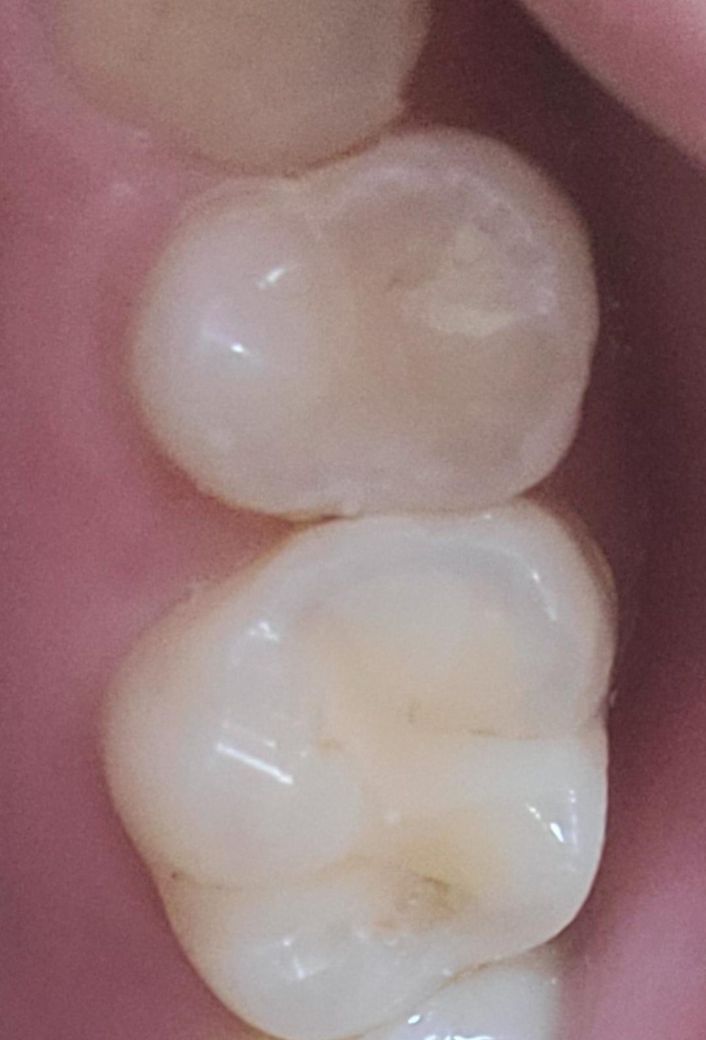

소구치와 대구치 사이가 까맣게 보여요.충치일까요?

제가 양치하고 치아를 살펴보니 소구치와 대구치 사이가 까맣게 보였습니다.

하지만 그 치아들은 9월에 레진치료를 받았고 10월에 충치확인을 위해 병원갔을 때도 별다른 이야기가 없었습니다. 하지만 그때 전체로 찍은 사진만 보셔서 조금 불안합니다.

혹시 치아사이에 충치가 생긴 걸까요?

아님 그냥 잇몸사이 틈새일까요?

약간 충치의 가능성도 있어보이지만 치아 사이는 엑스레이를 통해서 확인해보는 것이 좋습니다.

육안상으로는 충치가 아닐꺼 같긴합니다. 정확한건 치과에 가셔서 엑스레이를 찍어보셔야될것같습니다.

만약 해당 부위가 점점 넓어지거나, 통증 또는 불편감이 느껴진다면 충치가 생겼을 가능성도 있기에 상태를 보고 만약 불편감이 나타나는 경우에는 치과에 방문하여 상태를 확인하고 치료를 받길 권합니다.